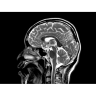

МР-томограф с широким туннелем Optima MR450w является настоящей рабочей лошадкой и может эффективно обслуживать большее число пациентов. Томограф обеспечивает одновременно удобство пациента, продуктивность работы, отличное качество изображения. В этой МРТ-системе инженерам компании удалось без компромиссов совместить необходимый объем перемещения с удивительно высоким качеством изображения.

«Правильные возможности», «Правильные условия», «Правильные инвестиции» — под таким девизом компания GE Healthcare представляет свой МР-томограф с широким туннелем Optima MR450w.

Требования пациентов к МРТ в последние годы изменились в сторону более качественного и комфортного сканирования. Увеличение размера туннеля — это шаг в правильном направлении, но только лишь первый шаг.

«Правильная» система должна преодолеть традиционные ограничения МР-томографов с широкими туннелями, сочетая в себе получение великолепных изображений и удобство при сканировании. Система должна обеспечить больший комфорт и пациентам во время сканирования, и врачам — при постановке точного диагноза. При этом организации вправе ожидать от используемых МР-томографов стабильной окупаемости финансовых затрат, соответствия высоким стандартам безопасности и повышения качества лечения пациентов.

Сканер Optima MR450w — это шаг в развитии МР-томографов с широкими туннелями, шаг в правильном направлении.